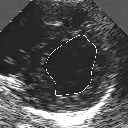

DETECTION AND TRACKING OF ANATOMICAL STRUCTURES USING DEFORMABLE TEMPLATES AND A NOISE MODEL ESTIMATION IN AN ECHOGRAPHIC SEQUENCE

In this work, we present a new method to shape-based segmentation of deformable anatomical structures in medical images and validate this approach by detecting and tracking the endocardial border in an echographic image sequence. To this end, a global prior knowledge of the endocardial contour is captured by a prototype template with a set of admissible deformations to take into account its inherent natural variability over time. In this approach, the data likelihood model rely on an accurate statistical modeling of the grey level distribution of each class present in the image. The parameters of this distribution mixture are given by a preliminary estimation step which takes into account the distribution shape of each class. Then the tracking problem is stated in a Bayesian framework where it ends up as an optimization problem. This one is then efficiently solved by a genetic algorithm combined with a steepest ascent procedure. This technique has been successfully applied on synthetic images and on a real echocardiographic image sequence. This method seems to be particularly well suited to handle ultrasound images with strong speckle noise on which edge information cannot be exploited. Finally, the local and global minimization procedure we propose is fast, robust and do not require initialization of the template close to the desired solution. Initialization may be defined at random, leading to segmentation and tracking procedure that are completely data driven. (slides)

Figure 1:   Tracking of the endocardial contour in a medical echographic sequence at different time frames during the cardiac cycle. From top left to bottom right : frame 1, 4, 6, 9, 12, 13, 18, 20, 27, 30, 35, 40, 41, 44, 46.